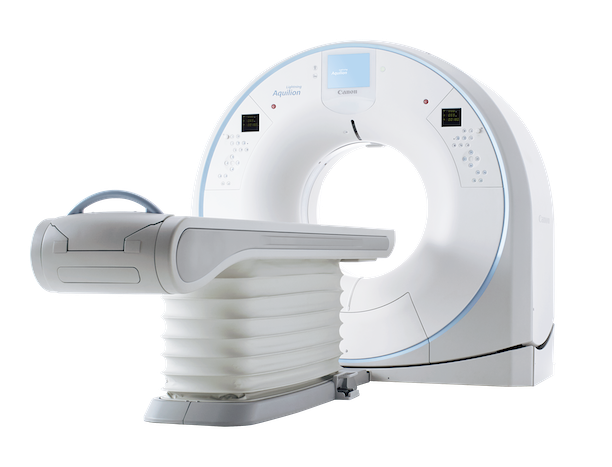

Amazon.co.jp: TK26-018 スカイイースト X線写真臨床検査の, X線検査装置(CT) : 分析計測機器(分析装置) 島津製作所,

SkyScan 1278 | Bruker, X線CT検査|神戸博愛病院(神戸市中央区),

X線CT検査|神戸博愛病院(神戸市中央区), xe-zenshini-h-2060-1.jpg,